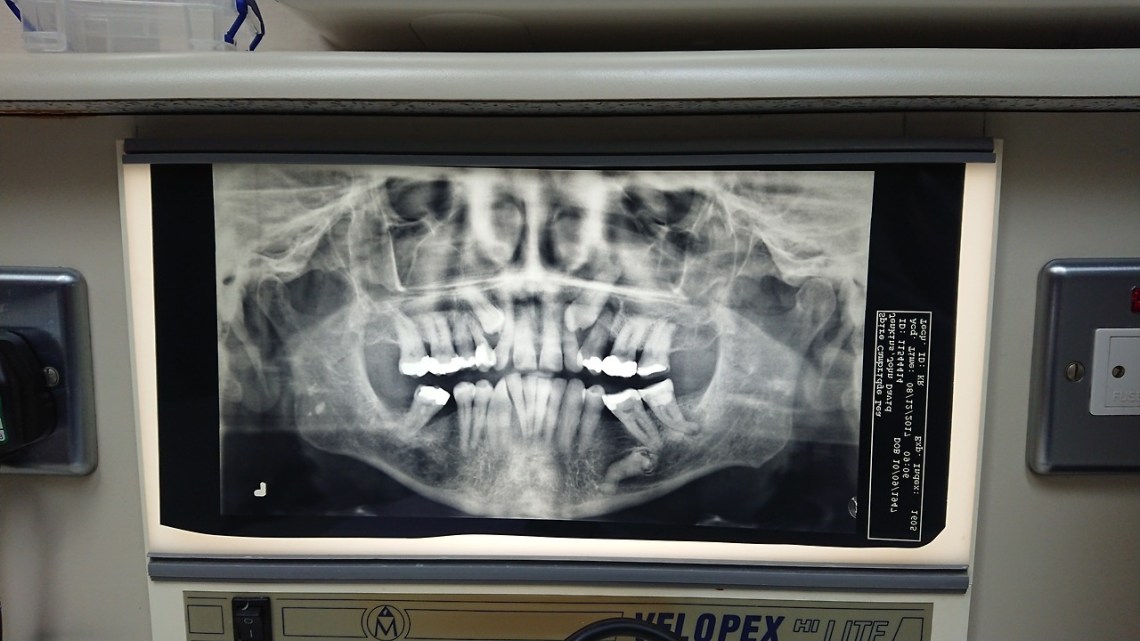

Fri 5 Jan 18: that’s my mouth and those are my teeth including the two ectopic ones which have never deigned to emerge. I agreed to allow the surgeon to take out the one on the right. It’s going to be some excavation …